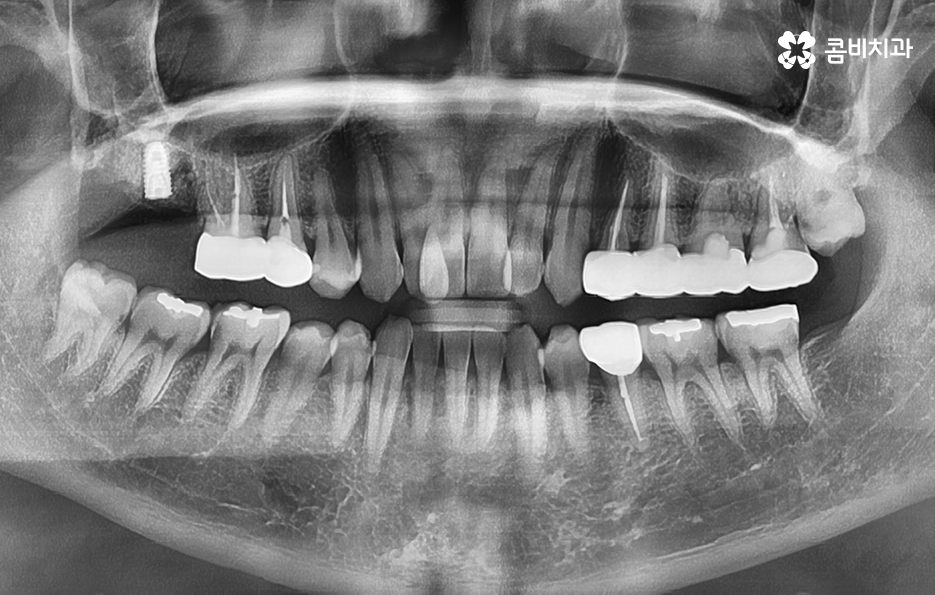

오늘은 자연치아를 결국 잃게 되면 대표적인 사례 중에서 오래된 보철물 혹은 보철물 관리가 잘 안되어 결국 발치로 이어지는 사례에 대해서 알아볼 거예요. 오래된 보철물 속에서 진행되는 2차 충치는 알아차리기도 쉽지 않고 이미 깊어지면 치아 뿌리 쪽으로 충치가 진행되어 발치로 이어지는 경우가 많다는 점에서 보철물 관리의 중요성에 대해서 재인식하는 포스팅이 되길 바라고 있어요

크라운 혹은 오래된 보철물 내부에 2차 충치가 발생된 경우에 자연치아를 보존할 수 있는지에 대한 판단은 엑스레이 만으로 진단할 수 있는 문제는 아니며 치아 내부에 충치가 어느정도나 진행되었고 잔존하는 치아의 양이 어느정도나 되는지에 따라서 발치 혹은 치아 보존 치료에 대한 판단을 할 수 있어요

이미 신경치료를 했던 치아라고 해도 보철물 제거 후에 충치를 잘 치료하고 재신경치료를 통해서 치아를 보존할 수 있는 경우가 있고 발치 후 임플란트를 해야하는 경우도 있는데요

이러한 판단 기준은 치아 내부에서 충치가 발생되었을 때 충치가 얼마나 치아 뿌리 쪽으로 깊어졌는지 혹은 살릴 수 있는 치아가 얼마나 잔존하는지에 따라서 다르며 치과의사 역시도 치아 속을 확인해보고 충치를 제거해봐야 알기 때문에 치과의사의 숙련도, 경험도 중요하겠지만 치과의 내원 시점이 무척이나 중요하기 때문에 보철물이 오래된 경우에는 꼭 주기적으로 치과 검진을 하시고 의사의 소견 하에 크라운의 교체가 필요하다면 문제가 커지기 전에 재치료를 적절히 받는 것이 자연치아 보존에 중요할 거예요

어금니 충치 발치 후에는 바로 임플란트를 해야 하나요

위 사진에서 보여지는 것처럼 어금니는 치아 안쪽에 위치하고 있기 때문에 치아 상실 후에 심미적인 부분에 있어서는 당장 불편함을 못느낄 수 있지만 치아는 저마다 역할과 기능이 있고 저작력에 있어서 밸런스도 무척이나 중요하기 때문에 치아를 잃게 되었다면 별다른 이유가 없다면 즉시 임플란트 치료 계획을 세우시길 권하고 있어요

당장은 반대쪽 어금니로 식사를 해도 괜찮다고 느끼시는 분들도 있지만 장기적으로는 치아 저작력의 밸런스를 잃게 될 수 있고 그로 인해 소화불량이나 턱 관절 장애로도 이어질 수 있는데요. 임플란트를 즉시 권하는 더 중요한 이유로는 치아 발치 후에는 해당 잇몸 뼈가 서서히 흡수되기 때문에 주변 치열이 망가지거나 반대쪽 치아가 내려올 수 있으며 추후에는 임플란트를 하더라도 잇몸 뼈의 부족으로 인해 뼈이식을 추가적으로 해야 할 수 있다는 점에서도 임플란트 치료를 미루지 마시길 권하고 있어요